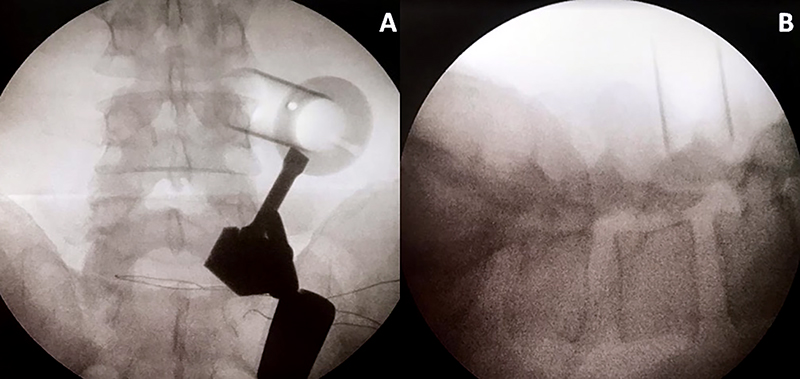

Todos los pacientes fueron operados bajo anestesia general y en decúbito prono con dos realces, uno a nivel torácico y el segundo en la pelvis. El brazo en C de radioscopia se coloca por debajo del paciente y el monitor se ubica los pies del mismo. El microscopio debe estar situado del lado opuesto al equipo de radioscopia. Se coloca un soporte en la barra lateral de la camilla, el cual sujetará posteriormente el brazo mecánico. Se realiza asepsia y colocación de campos estériles, con posterior localización del nivel a tratar con radioscopia. Realizamos una incisión paramediana de 2 cm. de largo, a 5 cm. lateral de la línea media. Luego se incide la fascia y se colocan los dilatadores correspondientes, para finalmente colocar un canal de trabajo de 20 mm. de diámetro (el largo dependerá de la contextura física de cada paciente). Se fija el canal de trabajo con el brazo mecánico cuando su ubicación se considera correcta.

El tubo debe dirigirse al espacio intertransverso del disco a tratar, teniendo como límites del espacio de trabajo, las apófisis transversas a nivel superior e inferior y las apófisis articulares medialmente. Esto se corrobora realizando radioscopia con incidencia anteroposterior y perfil (fig. 1).